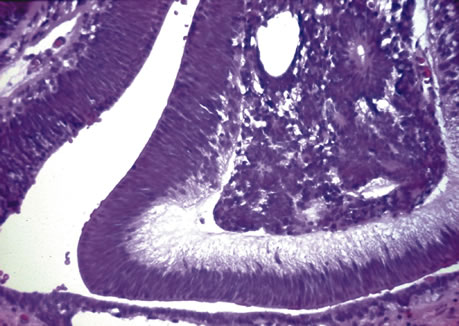

Persistant Hyperplastic Primary Vitreous, Trisomy 13-15

Persistent hyperplastic primary itreous (PHPV) is usually a unilateral condition that leads to fibrovascular connections in the retrolental area. These connections may reach the posterior retina and cause a severe tractional detachment. Adipose tissue, cartilage, and smooth muscle may be seen in the retrolental mass. Ciliary processes are stretched or elongated as well.49–54 A group of disorders characterized by trisomy 13-15 may also demonstrate the elongated ciliary processes and retrolental findings seen in PHPV.55–57 This condition (also termed Patau's syndrome) demonstrates retinal dysplasia and rosette-like configurations of the retina.